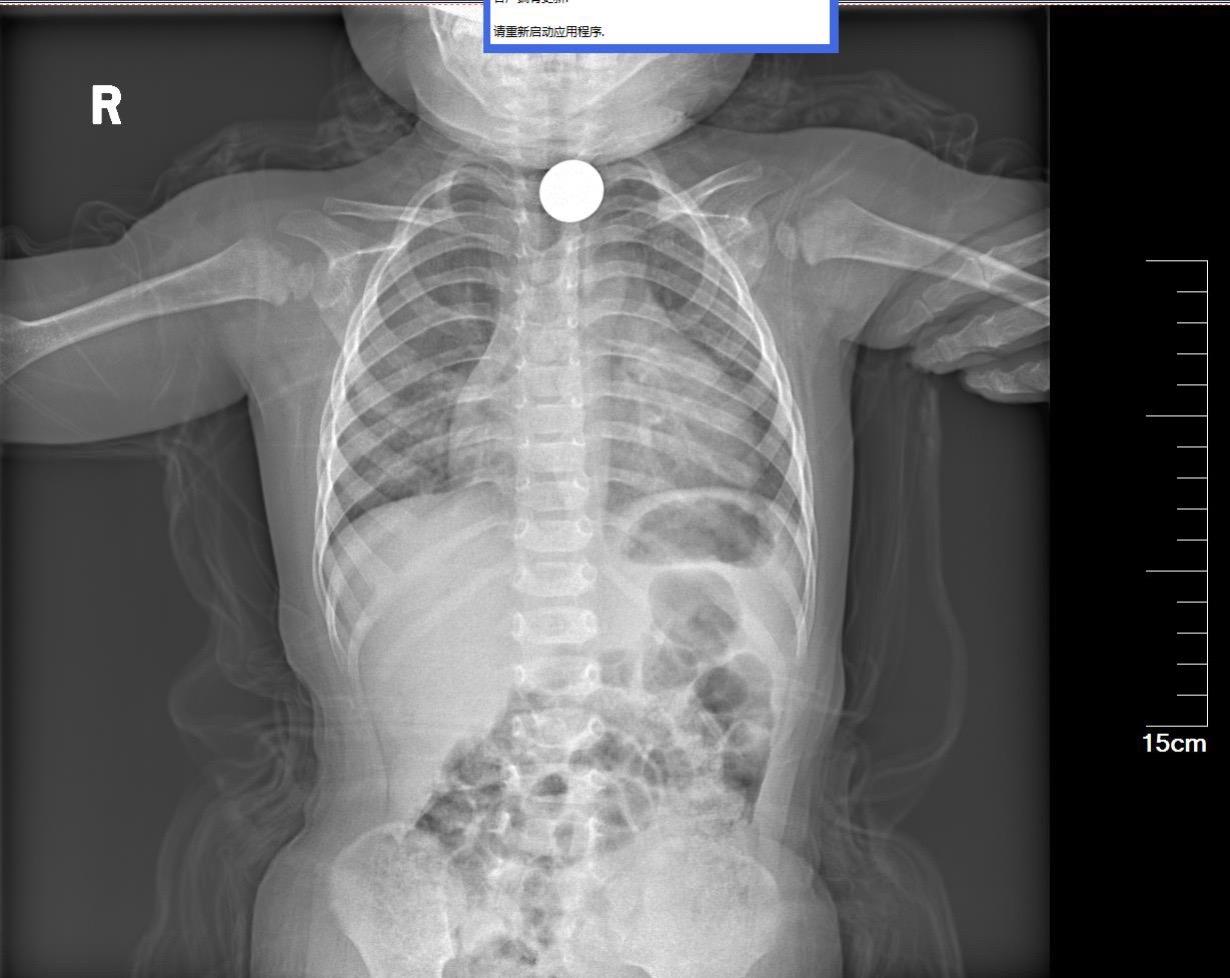

老年人吞咽不畅必有妖!老年人被鲍鱼卡住,做胃镜之前就怀疑是不好的病,胃...